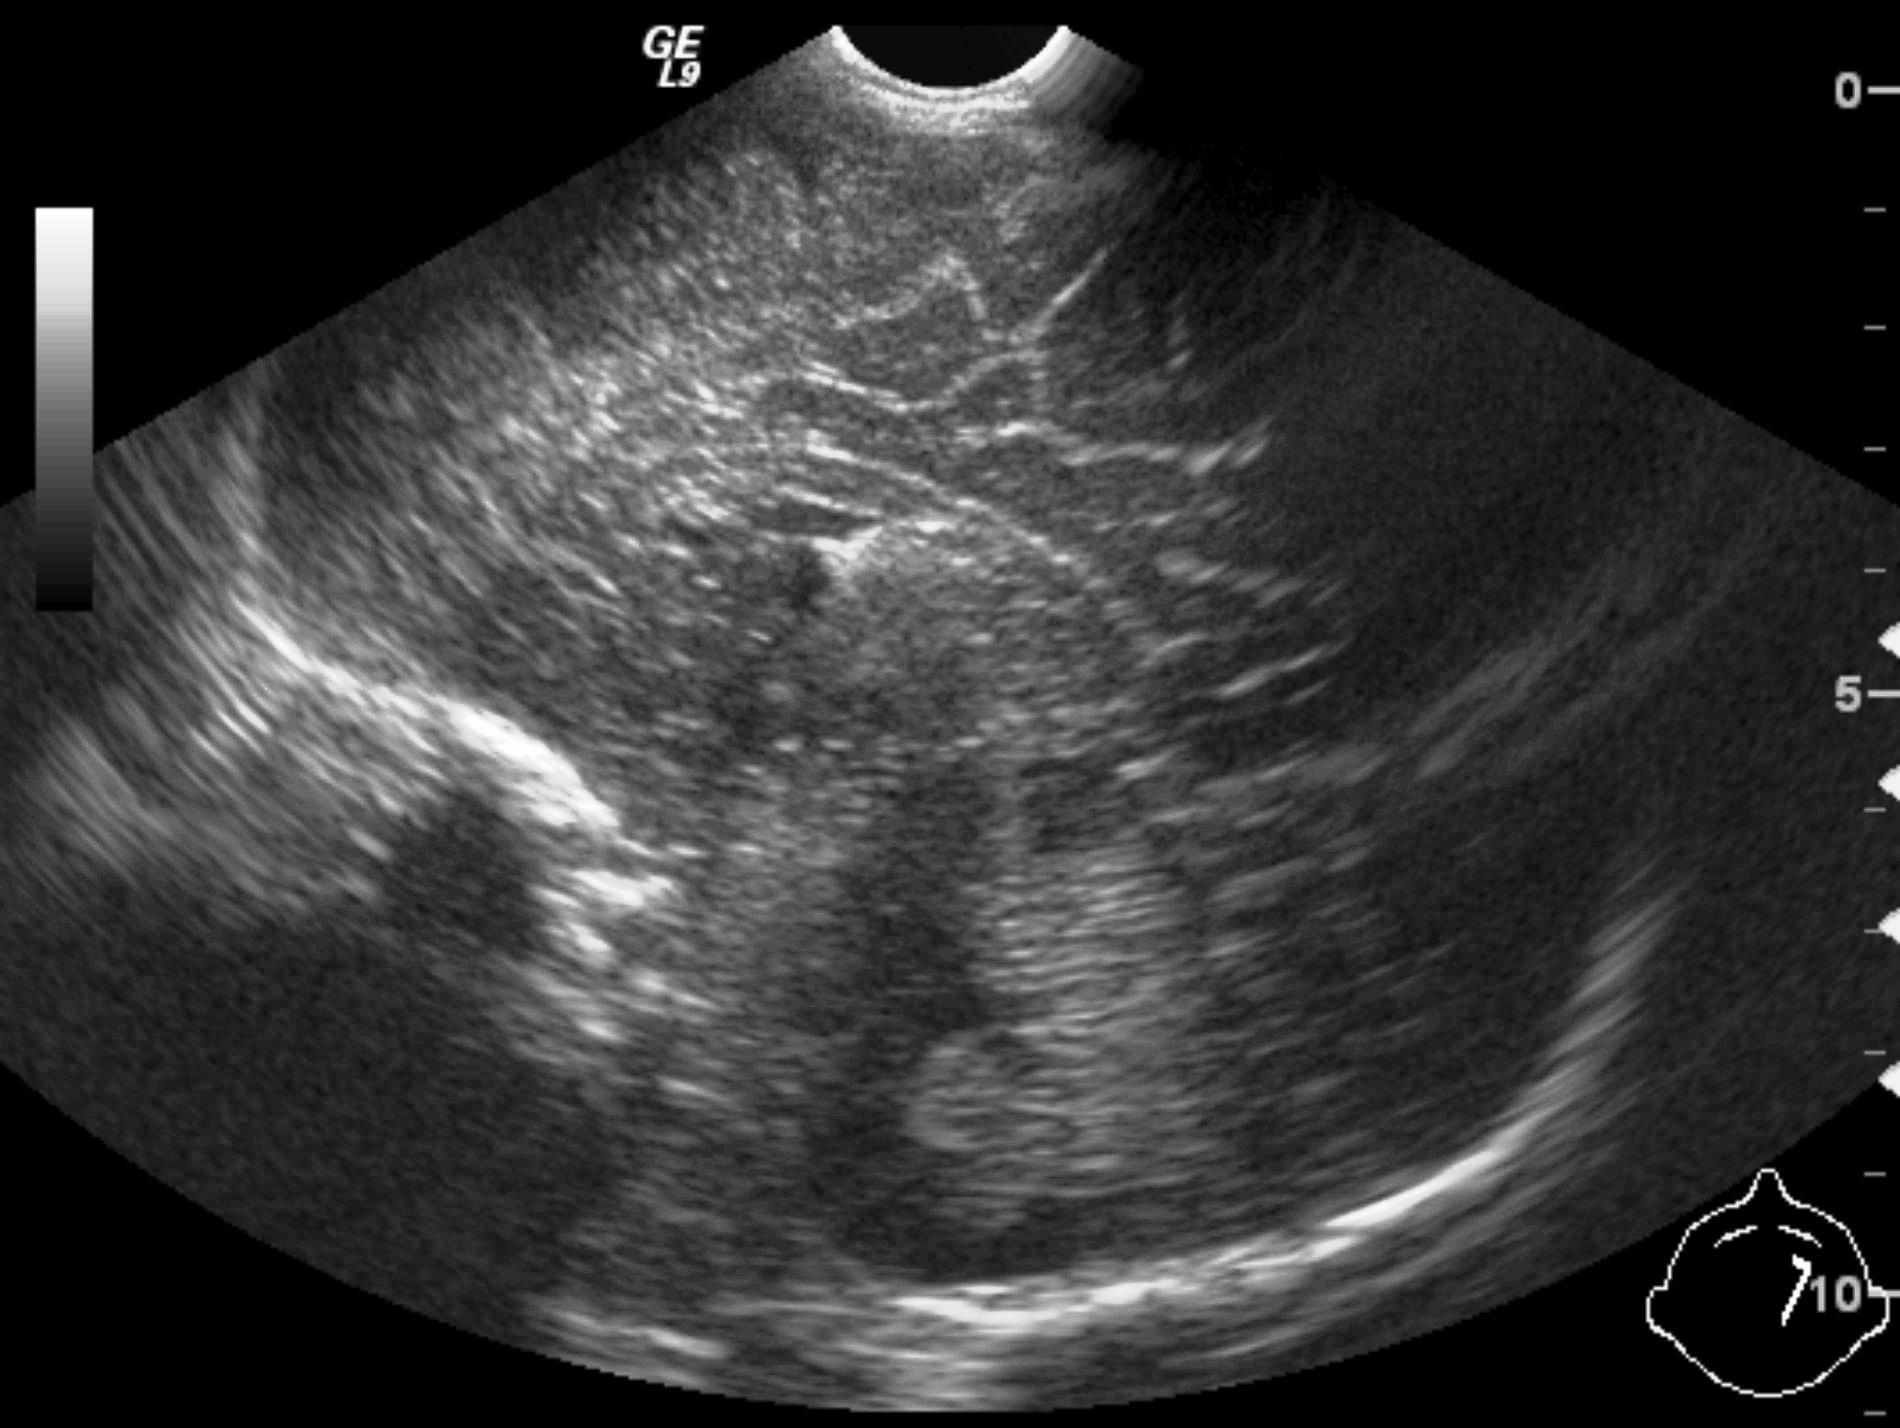

14. “Whirlpool” sign The mesentery and the superior mesenteric vein, as it coils around the superior mesenteric artery. Volvulus. US exam.

Image

15. Contrast material empties the stomach slowly, small intestines are found on the right side of the abdomen. Malrotation-volvulus.